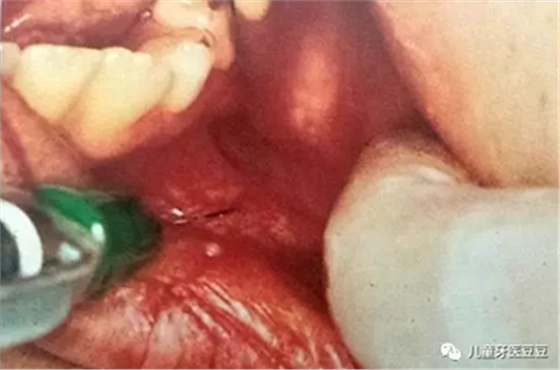

如果孩子在牙科治療中有過疼痛的經(jīng)歷,將會對他們將來一生的口腔治療產(chǎn)生影響,因此每次治療的時(shí)候應(yīng)將不適感降到最小,做到這點(diǎn)最有效的方法就是采用局部麻醉。

有些家長擔(dān)心麻醉會不會影響到孩子的大腦。其實(shí)兒童治療中常采用表面麻醉,浸潤麻醉和傳導(dǎo)麻醉,這些麻醉方法都是局部麻醉,主要作用于局部的牙齒、黏膜、骨,很少進(jìn)入血液,也自然對全身(包括大腦)影響很小。而且有經(jīng)驗(yàn)的醫(yī)生也會采用分散孩子注意力的方法讓孩子對局部麻醉注射的恐懼降到最低。

口腔局部浸潤麻醉